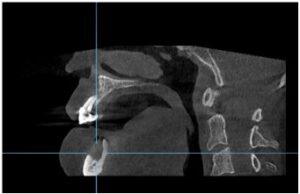

환자분께서는 19년도에

처음 본원에 내원하셨었는데

그 당시 양측 어금니가 거의 상실되어 있어

앞니와 작은 어금니 위주로

교합이 이루어지고 있는 상태였는데요.

그렇다 보니 무리한 교합력과

관리 부족으로

아래턱 오른쪽 송곳니(#43)가

만성 치주염으로

주변 잇몸뼈가 많이 약해져 있었습니다.

또한 왼쪽 송곳니(#33)와

두 번째 작은 어금니(#35)와 함께

long bridge 형태로

길게 묶어져 있는 상태로

해당 치아 역시 치아와 잇몸뼈를

단단히 잡고 있어야 할

치주 인대의 공간이

넓어져 있는 상태였는데요.

이 경우 예후가 좋지 않은

아래턱 오른쪽 송곳니(#43)는 발치하고

잔존 치아들은 잇몸 치료를 통해

염증이 더 진행되지 않도록

해주는 것이 중요하지만

환자분께서는 당시 치료를 진행하시지 않고

그대로 방치하셨으며,

증상이 더 심해지시자

3년이 지난 22년 4월 5일에

치료를 위해 다시 본원을 찾아주셨는데요.

먼저 구강 내를

확인해 보았더니

잇몸뼈 소실이 심해져

치아 뿌리가 노출되어 있는 상태로

Bridge로 연결된 치아 외에도

아래턱 왼쪽 큰 어금니도

동요도가 심한 상태였습니다.